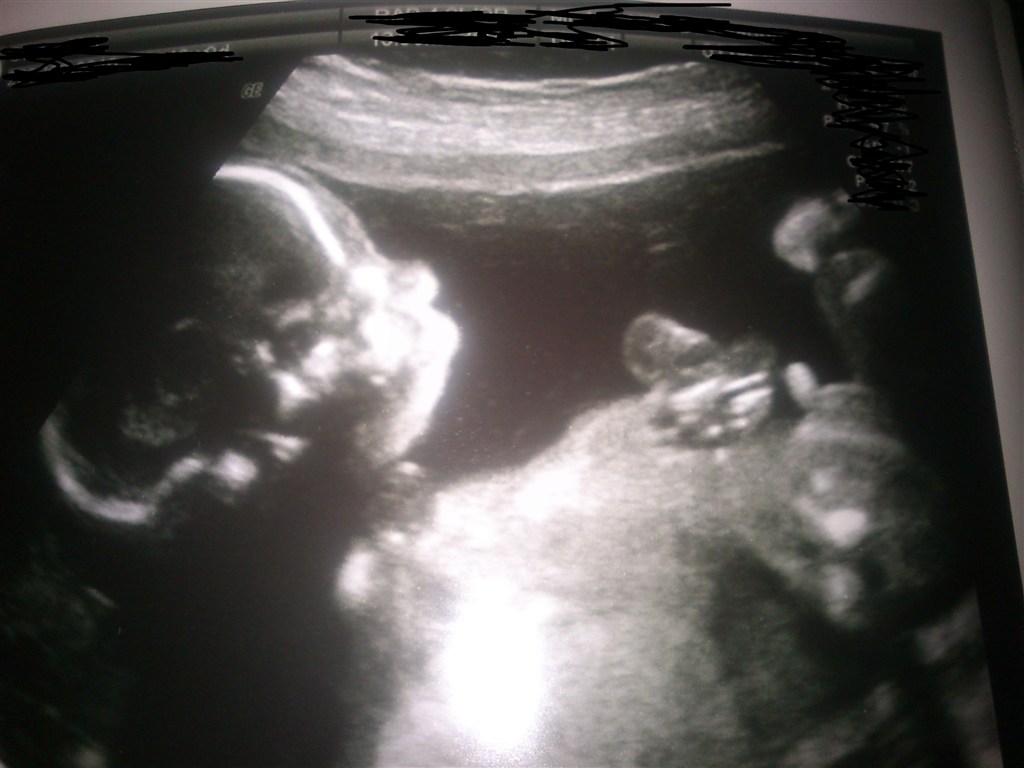

Så var vi til MD i dag, og vi venter også den dejligste lille Dreng

Han er helt perfekt

Han strittede meget med sin lille tap og lå med helt spredte ben, han ville bare have vi skulle vide det

Vi er halvejs imorgen, og vi glæder os så meget

I får lige et billed med på vejen

Der kommer lige et billed her

Vedhæftede fotos (klik for at se i fuld størrelse)

Hvor er det bare et godt billede af jeres lille dreng!

Hvor er det nogle fine billeder, og tillykke med den lille fyr Dejligt med et scannings billede, hvor man kan danne sig et indtryk af hvordan den lille ser ud